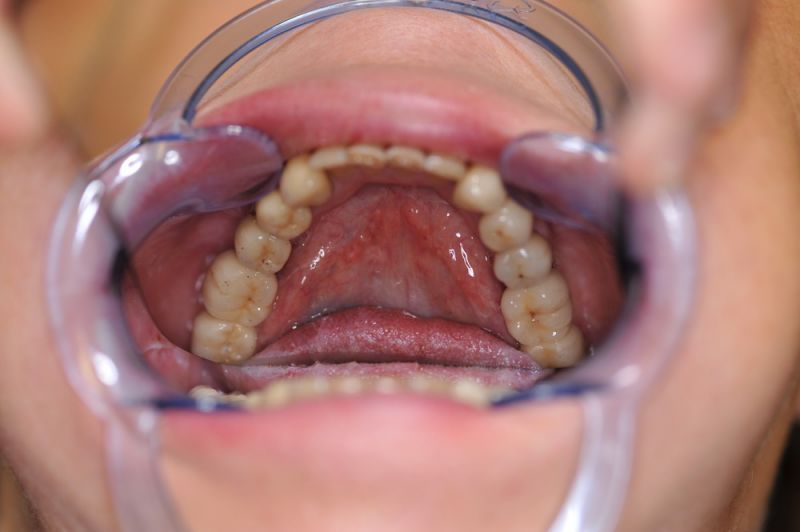

Alle 3 Monate Recall! Das ist jetzt Pflicht für diese Patientin und zwar so lange, so lange sie mit dieser Arbeit durch die Gegend laufen möchte! Und eiserne Disziplin bei der Mundhygiene!

Die Problematik der Implantatversorgungen kann man in einer Analogie folgendermaßen darstellen. Die räumlich beengten Zustände gleichen dem Tanz eines Paares auf einer Briefmarke, und der gleichzeitigen Schritt- und Fusshaltung, dass beim Tanzen die Schuhe geputzt werden können!